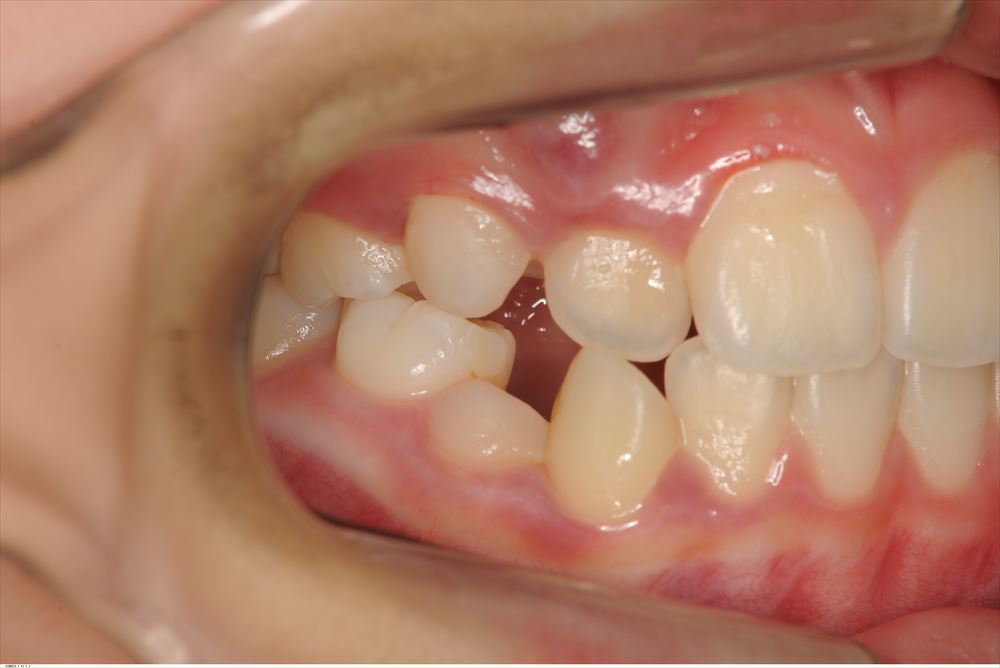

今日は矯正の装置を外した女の子。外してとても喜んで頂けました。

術前。あらま。

今日

リテーナー使ってねー。